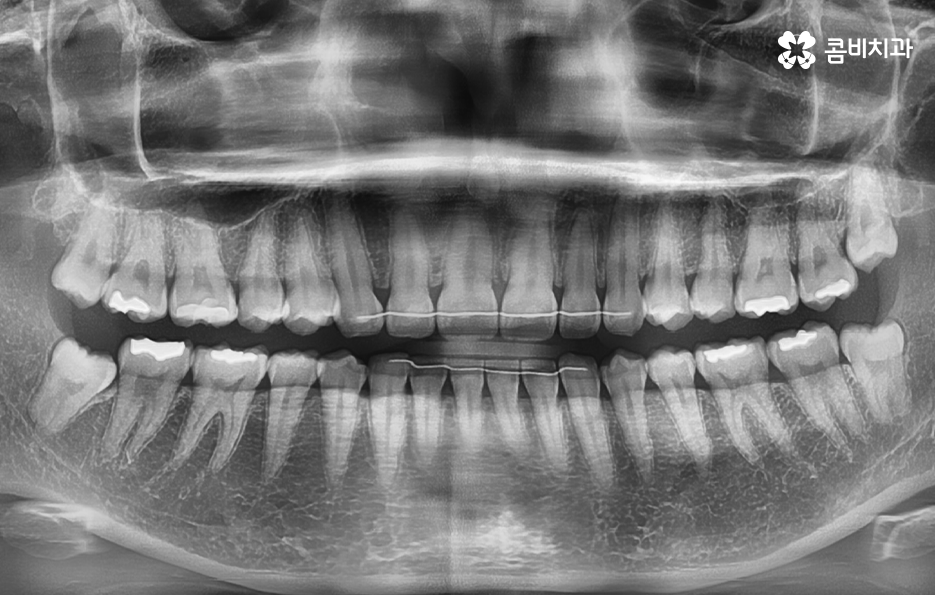

현대인들의 경우 사랑니가 4개 모두 나기 보다는 1~3개 씩 나는 경우도 많고 요즘 젊은 분들은 턱 뼈가 좁은 편인 분들이 많다보니 사랑니가 나올 공간이 부족하여 매복사랑니를 갖고 계신 경우도 많이 있어요

그리고 보편적으로는 윗니의 경우 중력에 의해 사랑니가 똑바로 나오는 경우가 좀더 많다면 아랫니의 경우 누워서 자라는 경우가 좀 더 많이 있는데요. 사랑니는 이처럼 나오는 위치나 방향의 개인차도 크고 정상적으로 똑바로 나온 경우에도 칫솔질이 잘 닿지 않거나 치석이 쌓이기 쉬운 위치이다 보니 결국 발치로 이어지는 경우가 많을 거예요

사랑니의 문제는 육안으로 상태 파악이 어려운 경우가 많기 때문에 주기적인 검진을 하지 않고 통증이나 매복사랑니 냄새와 같은 자각증상을 통해 치과에 방문하시면 치료가 복잡해지는 경우를 종종 볼 수 있는데요

매복사랑니의 경우 당장 발치가 필요하지 않은 경우에도 주기적으로 치과 검진을 통해 사랑니의 상태를 체크할 필요가 있으며 특히 어금니 뿌리 쪽에 안좋은 영향을 주고 있거나 우려가 있다면 발치 계획을 세워야 할 거예요